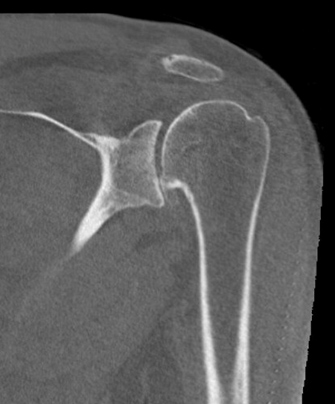

Pyrocarbon shoulder hemiarthroplasty

- Case Examples from Dr. Lee’s practice:

- This is a case example of a patient in his 40s who presented to us with severe shoulder pain, inability to work out and even raise his shoulder to chest level! At 6 months postoperatively he is back to the activities that he wants, keeping him active and healthy again